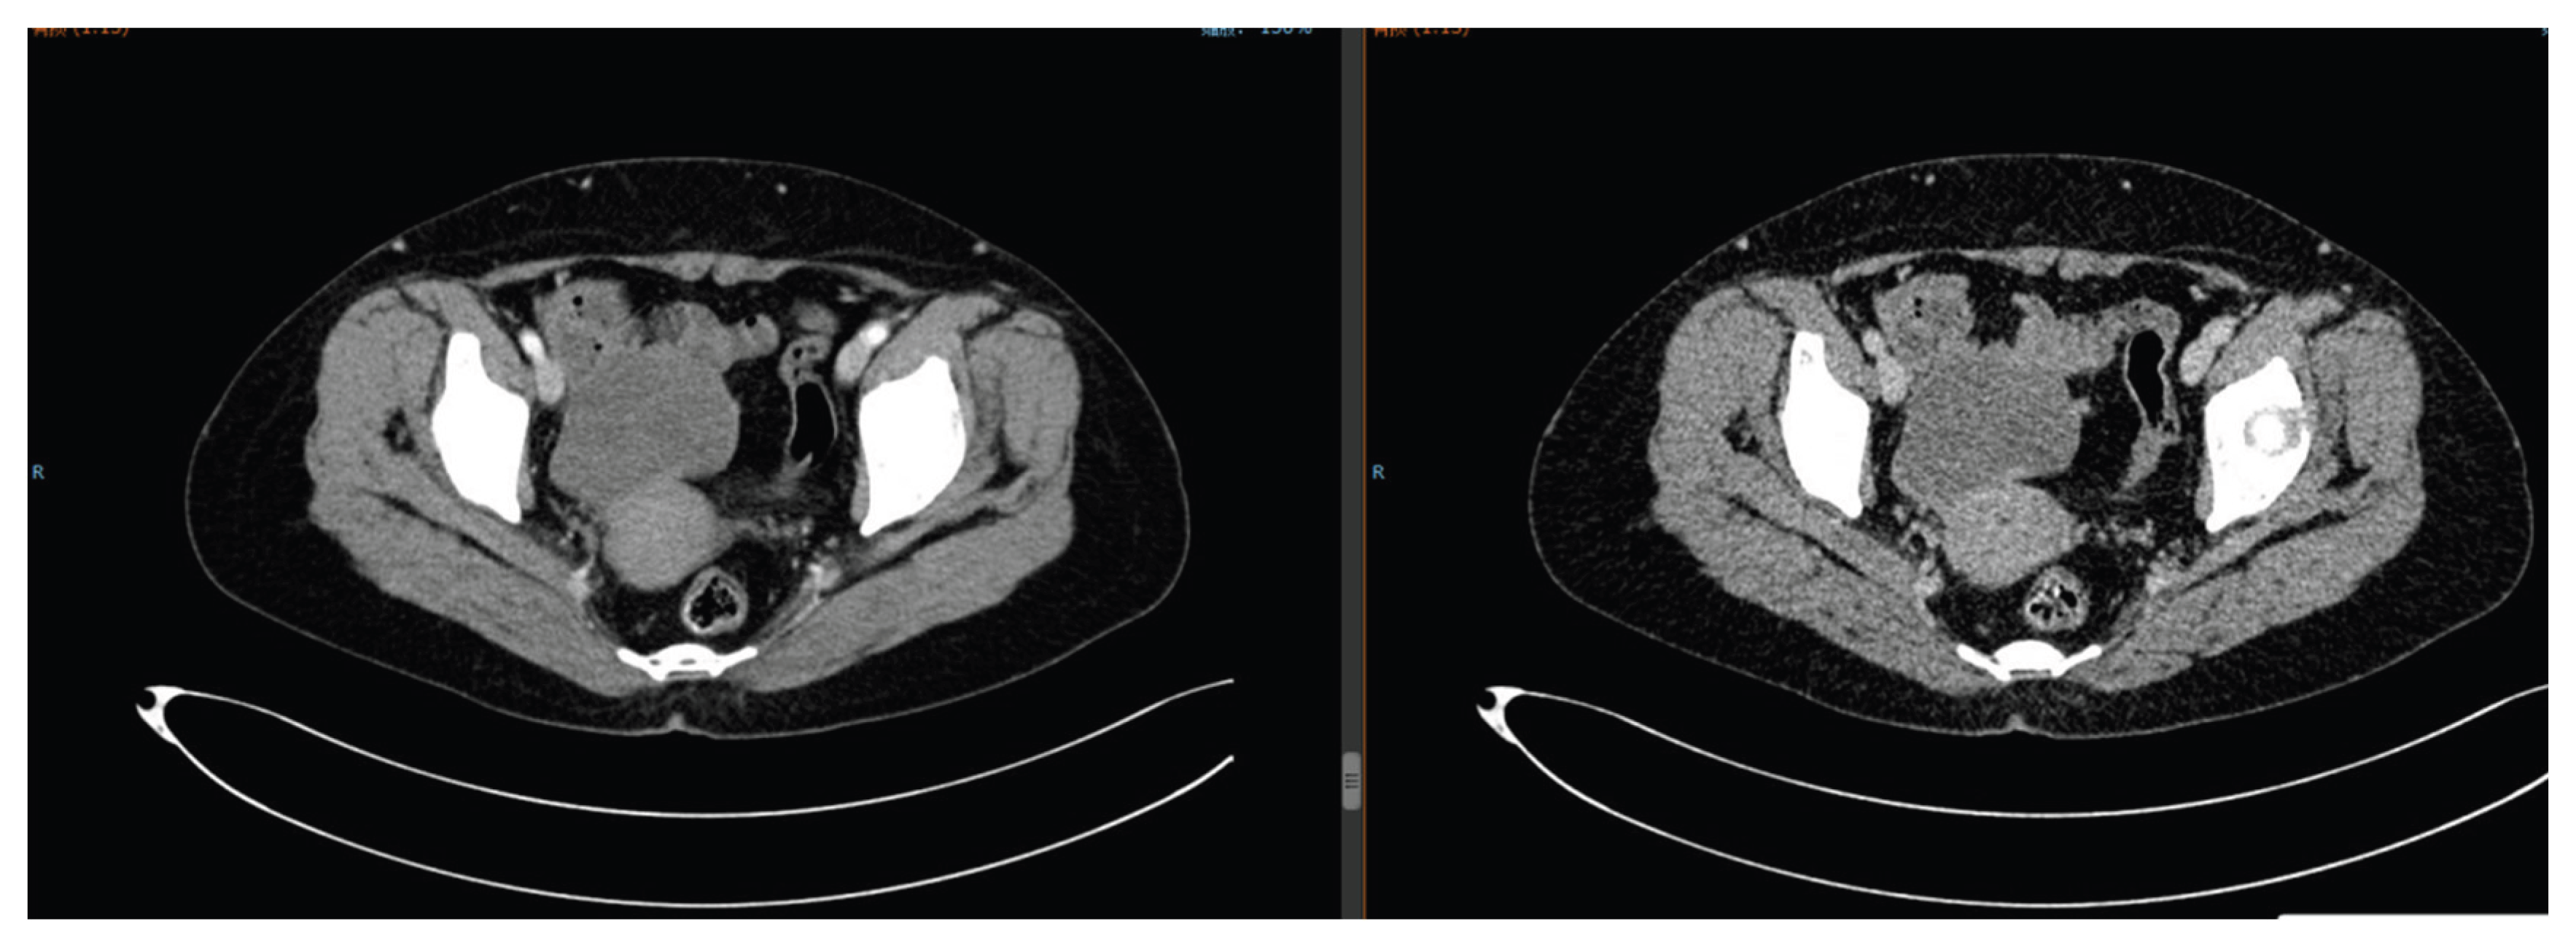

Figure 9. Pelvic CT on December 19, 2024: Partial response of ovarian tumor after HIFU and chemotherapy.

After a multidisciplinary team (MDT) discussion, she underwent HIFU treatment on September 9, 2024 (single dose: 3000 J, focusing on the ovarian lesion), followed by 4 cycles of docetaxel (80 mg ivgtt d1) + carboplatin (300 mg ivgtt d1) chemotherapy. The disease achieved PR (Figure 9), but she developed grade Ⅲ leukopenia (nadir white blood cell count: 1.9 × 109/L) and grade Ⅲ nausea/vomiting. The regimen was adjusted to single-agent docetaxel for 2 cycles, which she refused due to persistent gastrointestinal discomfort. Megestrol acetate dispersible tablets (160 mg orally once daily) were added. In May 2025, pelvic CT showed the tumor enlarged to 5.7 cm. Two cycles of pemetrexed disodium chemotherapy were administered, but the tumor further increased to 7.2 cm (Figure 10). The patient refused further chemotherapy and immunotherapy, continuing osimertinib for lung adenocarcinoma control.